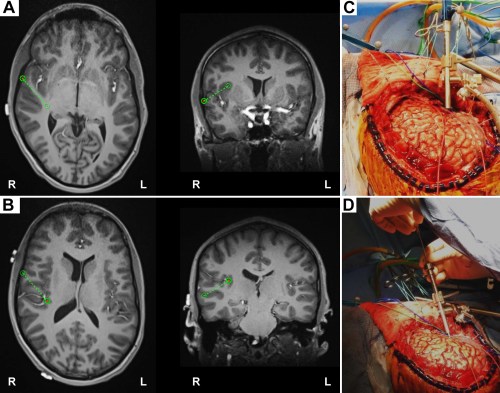

We can see how the endocranial EEG looks and how it gets done (WARNING: GRAPHIC) by referring to Nagahama et al (2019):

Intraoperative photographs demonstrating exposure and intracranial electrode placement. A right frontotemporoparietal craniotomy (A) allowed proper exposure for placement of grid, strip, and depth of electrodes (B), including the HG depth electrode. The sylvian fissure is marked with a dashed line. The HG depth electrode and PT depth electrose are marked with X symbols anteriorly and posteriorly, respectively, at their entry points at the cortical surface. Ant = anterior; inf = inferior; post = posterior; sup = superior.

Intraoperative placement of the HG depth electrode. A: The planning view on the frameless stereotactic system (Stealth Navigation, Medtronic) showing the entry point and the trajectory (green circles and dotted lines). B: The similar planning view showing the target and the trajectory. C and D: Intraoperative photographs showing placement of the HG depth electrode. A Stealth Navigus probe was used to select the appropriate trajectory of a guiding tube positioned over the entry point (C). An electrode-guiding cannula was advanced through the tube to the previously determined depth (D). An actual depth electrode was subsequently passed through the cannula, followed by removal of the guiding tube/cannula system. Note the unique anterolateral-to-posteromedial trajectory within the STP for placement of the HG depth electrode.